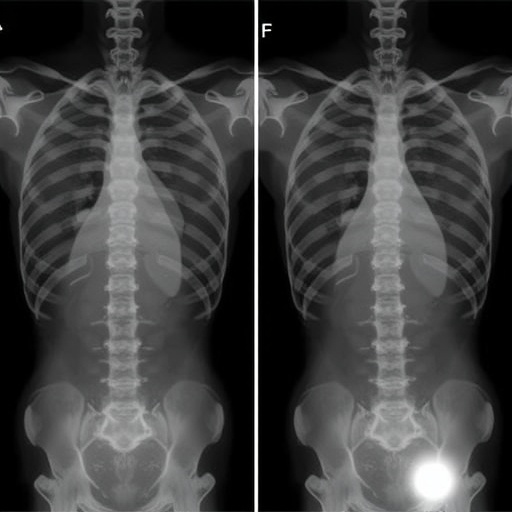

The T1 slope, an angle defined by the orientation of the T1 vertebral endplate relative to a horizontal plane, is a crucial anatomical parameter reflecting the global sagittal alignment of the cervical spine. Cervical lordosis, the natural backward curvature of the cervical spine, is integral to maintaining the biomechanical equilibrium necessary for function and pain mitigation. The difference between these two measurements—T1S-CL—emerges as a nuanced indicator of how well the cervical spine is balanced relative to its thoracic base. The study posits that this parameter, when evaluated preoperatively, serves as a quantifiable surrogate for the biomechanical stress that the cervical spine bears post-surgery.

This research prospectively enrolled elderly patients diagnosed with DCM, all slated for standalone laminectomy, rigorously collecting preoperative radiographic data alongside comprehensive clinical evaluations. Utilizing advanced imaging techniques and sophisticated angle calculations, the researchers measured T1 slope and cervical lordosis to derive the T1S-CL value. Postoperative outcomes were meticulously tracked using standardized neurological function scales and quality-of-life questionnaires over extended follow-up periods, ensuring robust correlation analyses between preoperative spinal alignment and recovery trajectories.